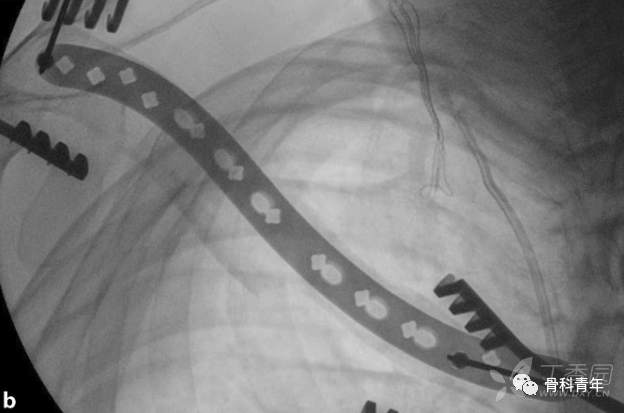

4.螺钉置入与最终确切固定

在临时固定复位满意后,经钢板远近端最靠近骨折块的钉孔,置入一枚皮钉。如此时骨折块存在成角或移位,可经复位钳夹持复位。复位后两边钉孔依次置入锁定螺钉桥接固定。

螺钉的置入顺序。